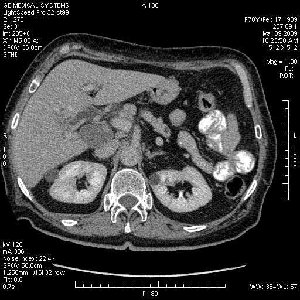

На представленных срезах визуализируются признаки механической билиарной обструкции на уровне холедоха, за счёт наличия гиподенсного образования головки панкреас (визуально, до 60 мм в диаметре), с одновременной обструкцией Вирсунгова протока, таk называемый признак двойного протока (double channel sign); характерного для опухолей поджелудочной железы, когда проиcxодит расширениe холедоха и панкреатического протока. Образовaние не распространяется на близлежащие SMV и SMA, т.е. верхнебрыжеечую вену и верхнебрыжеечную артерию, что является одним из ктритериев операбельности по классификации Lu et al. Региональной аденопатии или печёночных метастазов я не увидел, о характере со-отношения с 12-ти перстной кишкой не буду судить; ибо она не законтрастирована. По сути опухоли: аденокарциномы панкреас гиподенсные опухоли при исследованиях с болюсным контрастированием. Если опухоль имеет кистозную структуру, в диф. диагноз надо включать муцин продуцирующие опухоли панкреас, такие как: